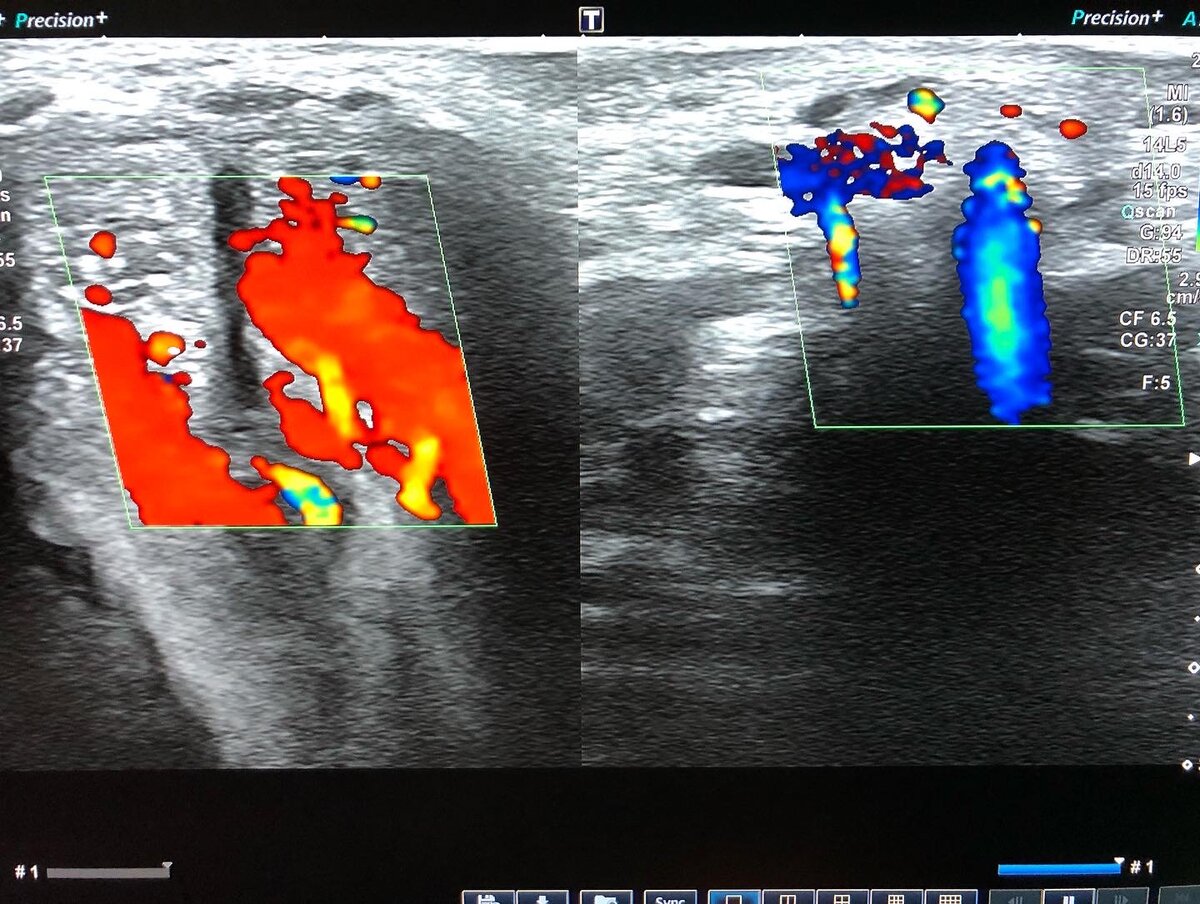

🔺Артериогенная ЭД является возрастной патологией, так как атеросклеротические изменения коронарных и пенильных артерий идентичны.

✅В раннем возрасте артериогенная ЭД может наступить из-за врождённых аномалий сосудов, курения, гипертонической болезни, сахарного диабета или вследствие травмы.

✅Недостаточный приток артериальной крови не способен полноценно питать КТ и эндотелий сосудов, нарушается местный обмен веществ, что может привести к необратимым дисфункциональным расстройствам КТ.

🔺Развитию веногенной ЭД способствуют нарушения в венозном кровяном русле, при которых просвет вен увеличивается.

✅Это случается при эктопическом дренировании КТ через венозные сосуды пениса, при травматических разрывах белочной оболочки, в результате чего развивается её недостаточность.

✅Веногенная ЭД часто сопутствует Болезни Пейрони и функциональной недостаточности кавернозной эректильной ткани.